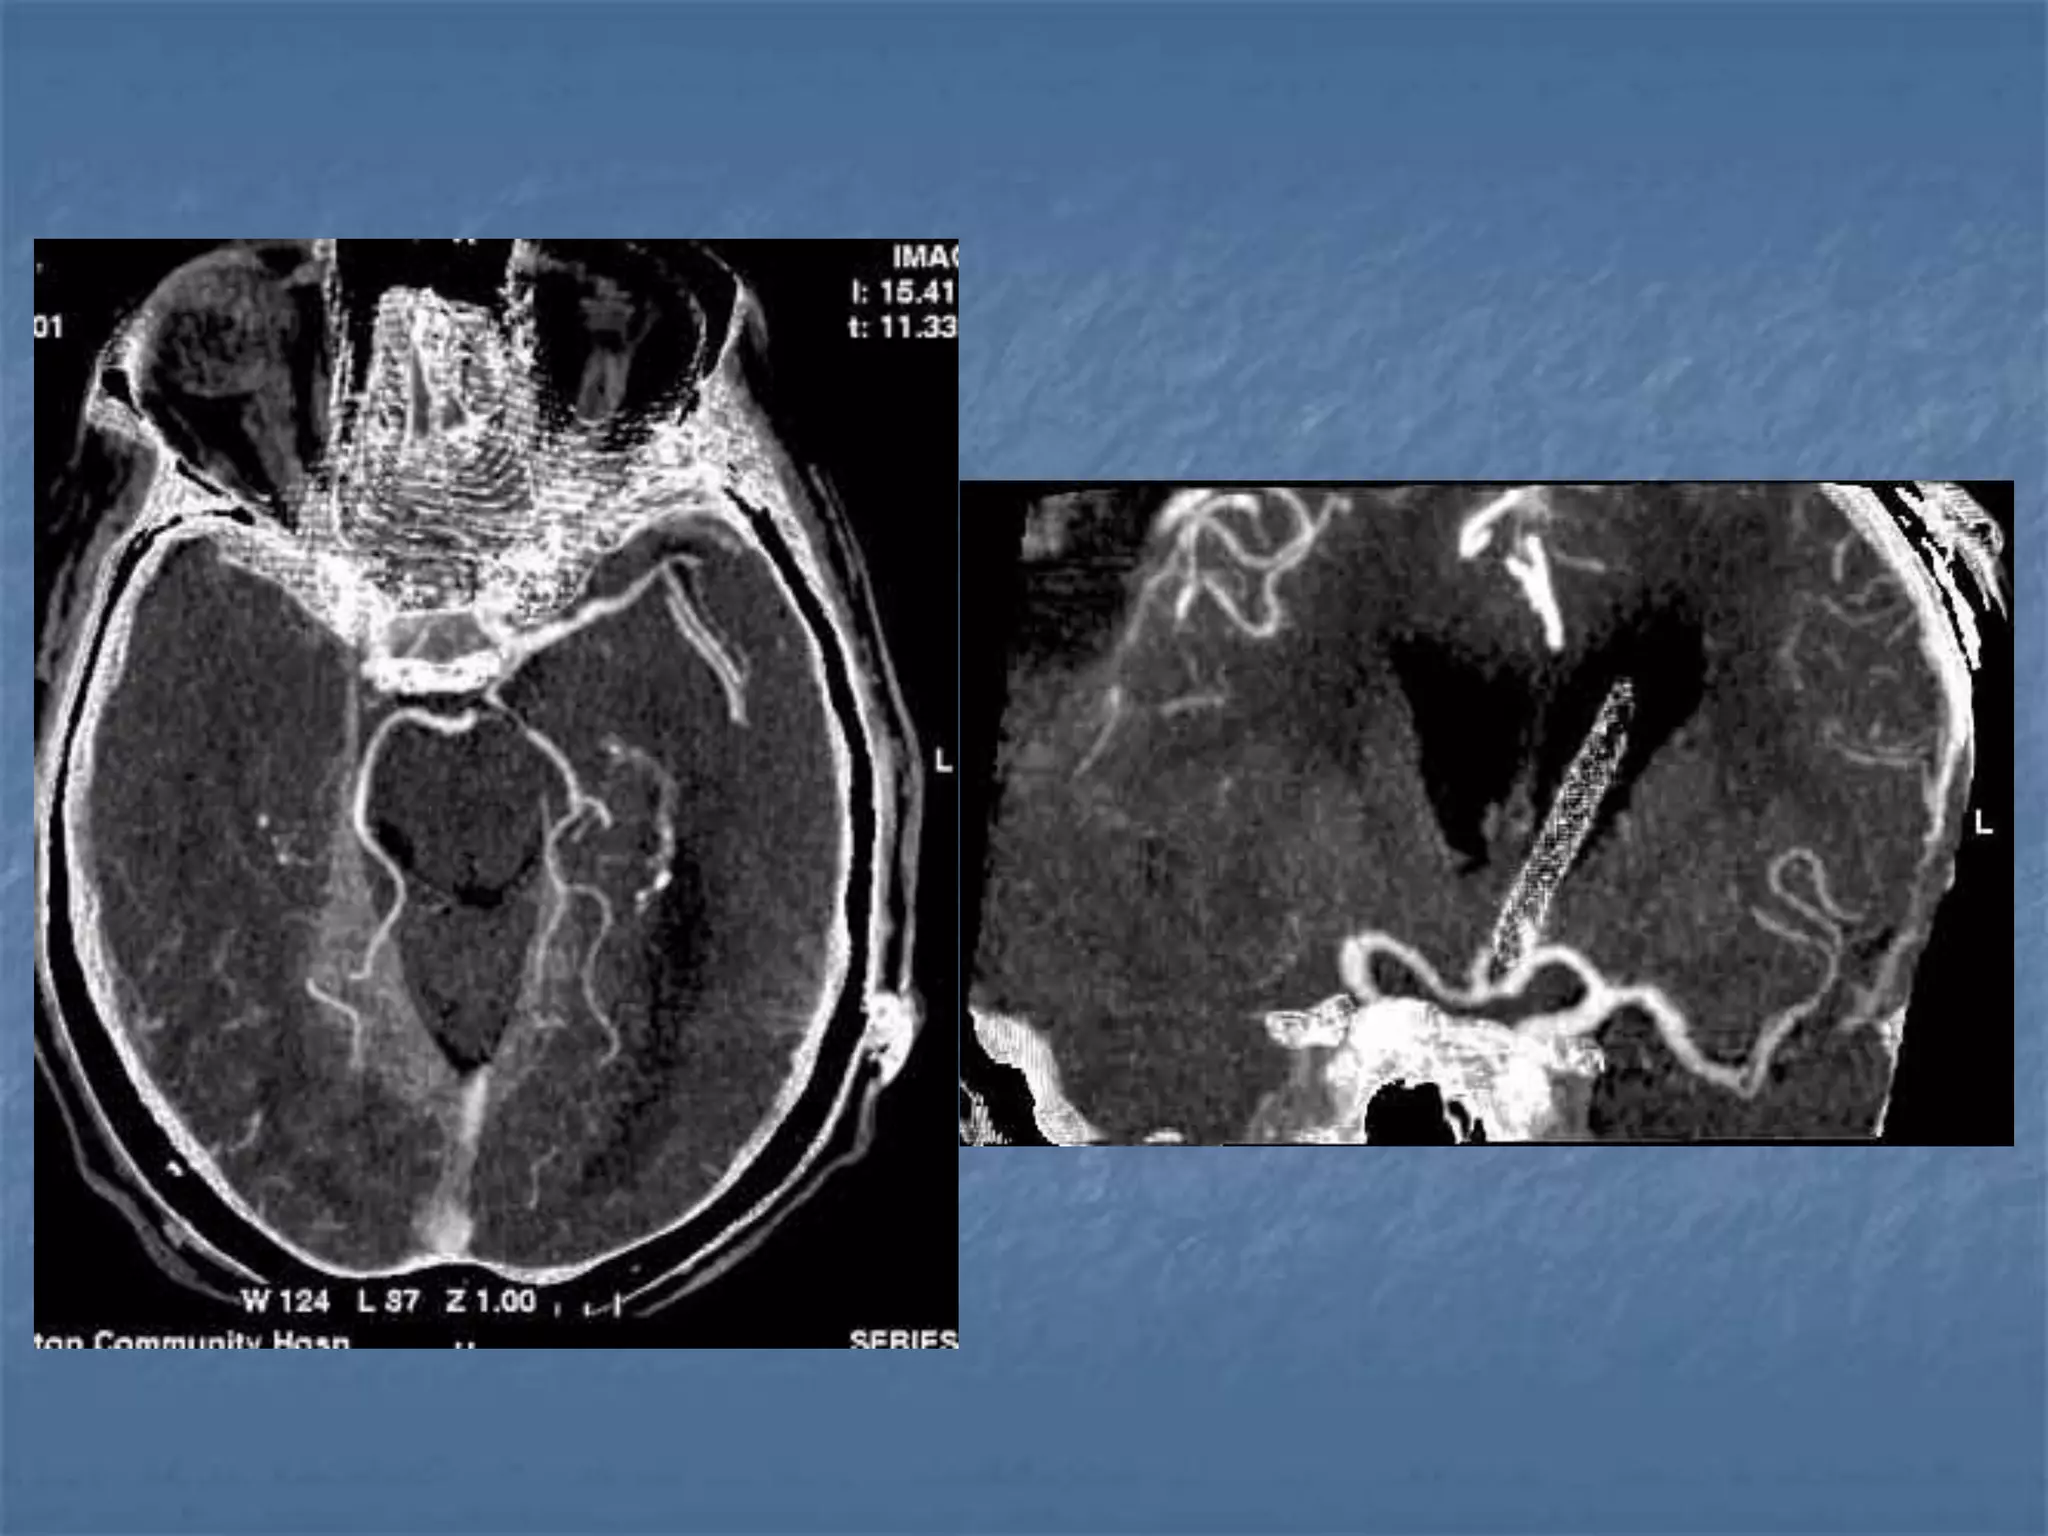

CT Angiography

 Site of occlusion

 Length of occluded

segment

 Arteries beyond occluded

segment – collateral flow

 Detection & exclusion of

large vessel intracranial

occlusion – sens – 98.4%

and spec.-98.1%

JCAT 2001; 25(4):520-8

Subarachnoid hemorrhage

 In the absence of trauma, the most common cause

of subarachnoid hemorrhage is a ruptured cerebral

aneurysm. Cerebral aneurysms tend to occur at

branch points of intracranial vessels and thus are

frequently located around the Circle of Willis.

Common aneurysm locations include the anterior

and posterior communicating arteries, the middle

cerebral artery bifurcation and the tip of the basilar

artery. Subarachnoid hemorrhage typically presents

as the "worst headache of life" for the patient.

Detection of a subarachnoid hemorrhage is crucial

because the rehemorrhage rate of ruptured

aneurysms is high and rehemorrhage is often fatal.

 CT is currently the imaging modality of choice because

of its high sensitivity for the detection of subarachnoid

hemorrhage. CT is most sensitive for acute

subarachnoid hemorrhage. After a period of days to

weeks CT becomes much less sensitive as blood is

resorbed from the CSF. If there is a strong clinical

indication, LP may be warranted despite a negative CT

since small bleeds can be unapparent on imaging.

On CT, a subarachnoid hemorrhage appears as high

density within sulci and cisterns. The insular regions

and basilar cisterns should be carefully scrutinized for

subtle signs of subarachnoid hemorrhage.

Subarachnoid hemorrhage may have associated

intraventricular hemorrhage and hydrocephalus.